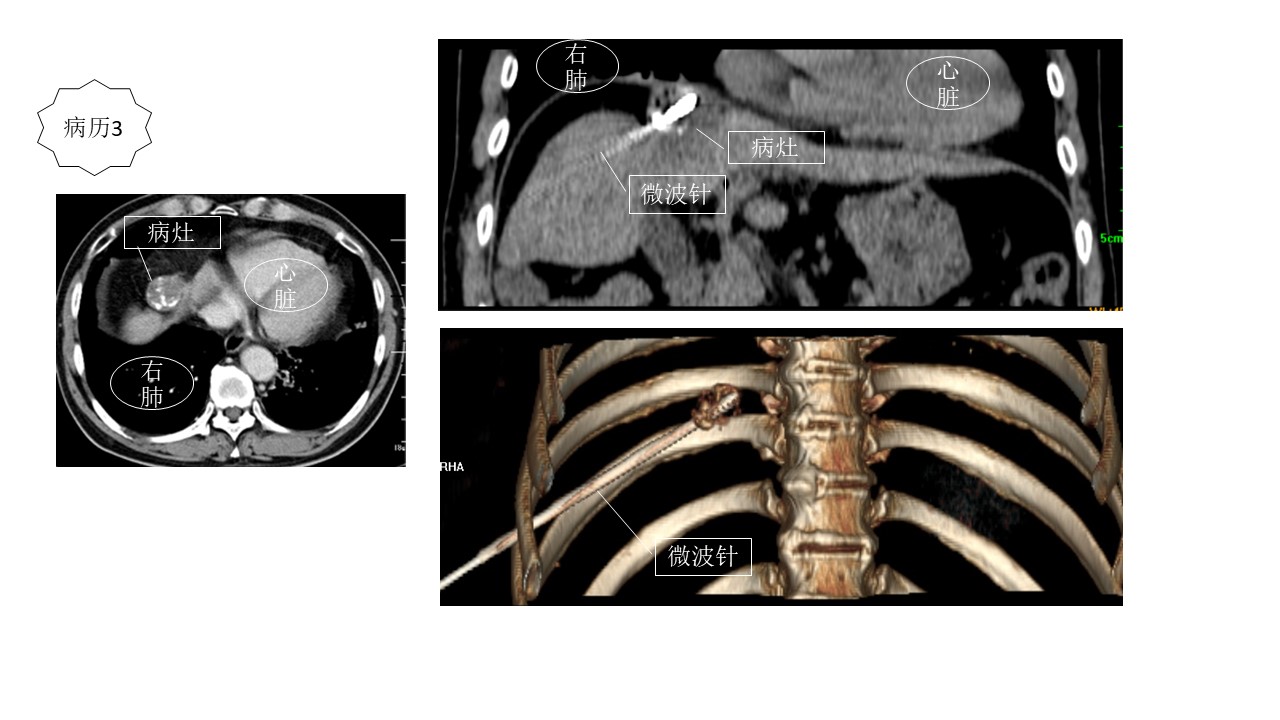

病历3。男,58岁,乙肝、肝硬化、肝癌。外科切除后复发。病灶位于膈顶,紧邻心脏,且被右肺包饶。我们利用电磁导航系统,从右肋下倾斜穿刺,准确布针,彻底消融。